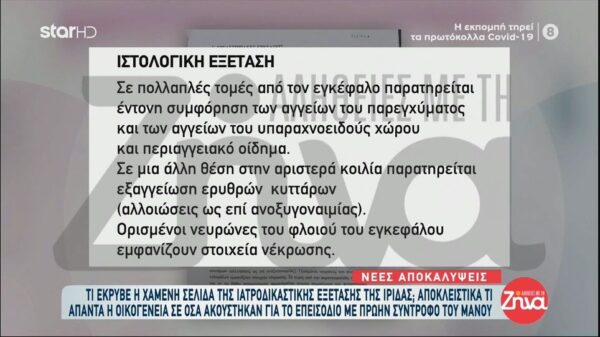

Aποκάλυψη για την υπόθεση της Πάτρας: Όλα όσα έκρυβε η χαμένη σελίδα της ιατροδικαστικής εξέτασης της Ίριδας

Όλες οι τελευταίες εξελίξεις στο θρίλερ της Πάτρας.